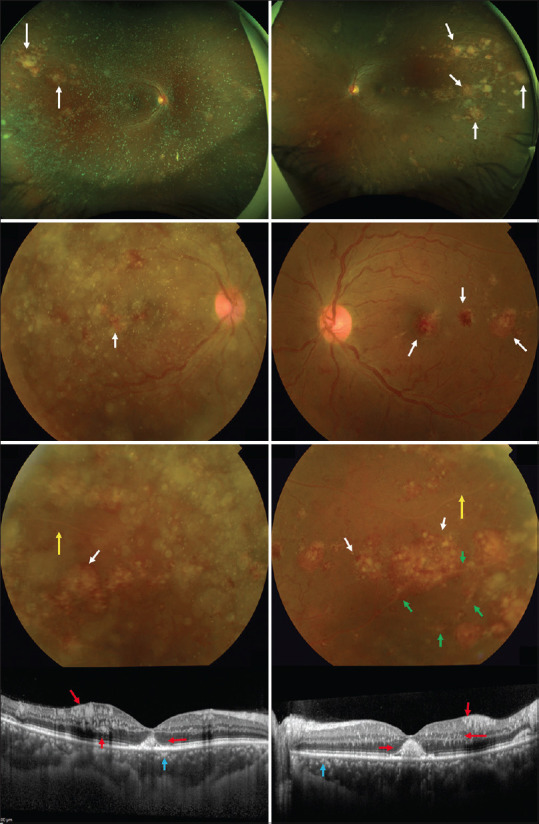

Chronic myeloid leukemia (CML) is a malignant proliferative disorder involving the bone marrow and lymphatic system. Retinal involvement is a rare form of presentation in patients with CML. We report a case of a 49-year-old woman who presented with an acute bilateral visual disturbance. Her initial visual acuity was 20/20 in both eyes. Fundus examination revealed multiple yellowish retinal infiltrates, vascular sheathing, and peripheral sclerosed blood vessels. Fundus fluorescein angiography revealed bilateral peripheral retinal ischemia. Optical coherence tomography of the macula showed varying sizes of hyperreflective lesions distributed within the inner and outer retinal layers and in the subretinal space. Systemic workup revealed marked leukocytosis, and bone marrow biopsy revealed CML. Patients with CML can rarely present with ocular symptoms. Early recognition and prompt referral are crucial in lifesaving.

慢性髓性白血病(CML)是一种累及骨髓和淋巴系统的恶性增生性疾病。视网膜受累是 CML 患者的一种罕见表现形式。我们报告了一例因急性双侧视力障碍而就诊的 49 岁女性病例。她最初的双眼视力为 20/20。眼底检查发现多处淡黄色视网膜浸润、血管鞘和周围硬化血管。眼底荧光素血管造影显示双侧周边视网膜缺血。黄斑的光学相干断层扫描显示,视网膜内外层和视网膜下间隙分布着大小不等的高反射病变。全身检查发现白细胞明显增多,骨髓活检显示患有慢性骨髓性白血病。CML 患者很少会出现眼部症状。早期识别和及时转诊对挽救生命至关重要。